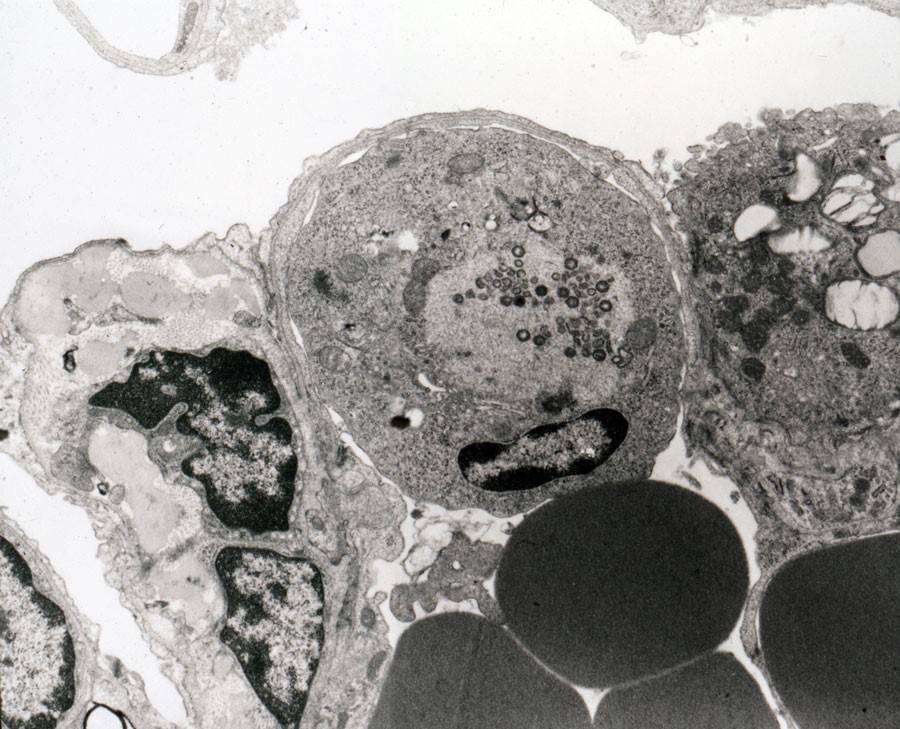

Макрофаг, пораженный вирусом африканской чумы свиней

Проникнув организм поросенка, взрослой особи, возбудитель поражает макрофаги., что приводит к активации транскрипции свободных генов для ответной реакции организма. Ллокализуется вирус АЧС в эндотелиьальных клеточных структурах кровеносных, лимфатических сосудах, в мононуклеарных фагоцитах, миелоидных, лимфоидных тканях органов иммунной системы.

Вирус, по мере увеличения его количества в организме больных животных, оказывает цитопатическое воздействие на лимфоциты, эндотелиальные клетки. Со временем развивается некроз сосудистых стенок, увеличивается порозность сосудов. Репродукция вируса сопровождается цитопатическим действием на лимфоциты, макрофаги и эндотелиальные клетки.

Вследствие фибриноидного некроза эндотелия кровеносных сосудов резко повышается проницаемость стенок сосудов, появляются венозная и воспалительная гиперемия, тромбозы, лейкопения.